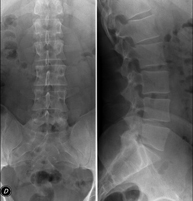

Tècnica que usa els raigs X a través de la qual s'obtenen imatges de la columna dorsal per al seu estudi. Indicacions: traumatisme, mal d'esquena. - RX Columna lumbar

Tècnica que usa els raigs X a través de la qual s'obtenen imatges de la columna lumbar per al seu estudi. Indicacions: ciàtica, traumatisme, dolor lumbar. - RX Sacre-còccix

Tècnica que usa els raigs X a través de la qual s'obtenen imatges de tota la columna vertebral per al seu estudi, amb la valoració especialment de la presència d'escoliosi i dismetries pèlviques.